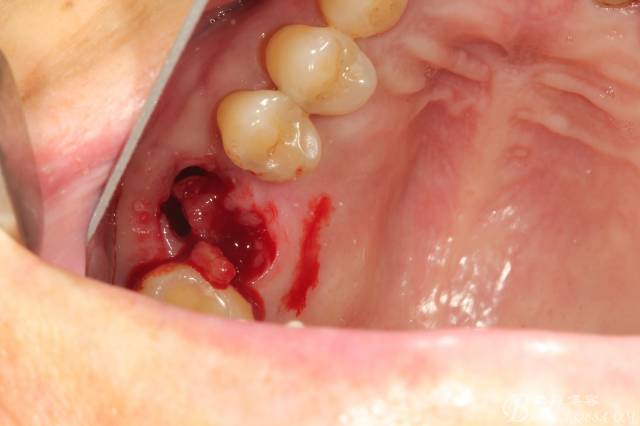

先26號牙位拔牙前照片顯示牙根頰舌向已經(jīng)裂開

拔牙后拔牙窩里面大量肉芽組織

清理拔牙窩 清理的非常干凈包括齦緣周圍牙齦適當(dāng)修整后看到拔牙窩是巨大的,牙槽中隔已經(jīng)吸收